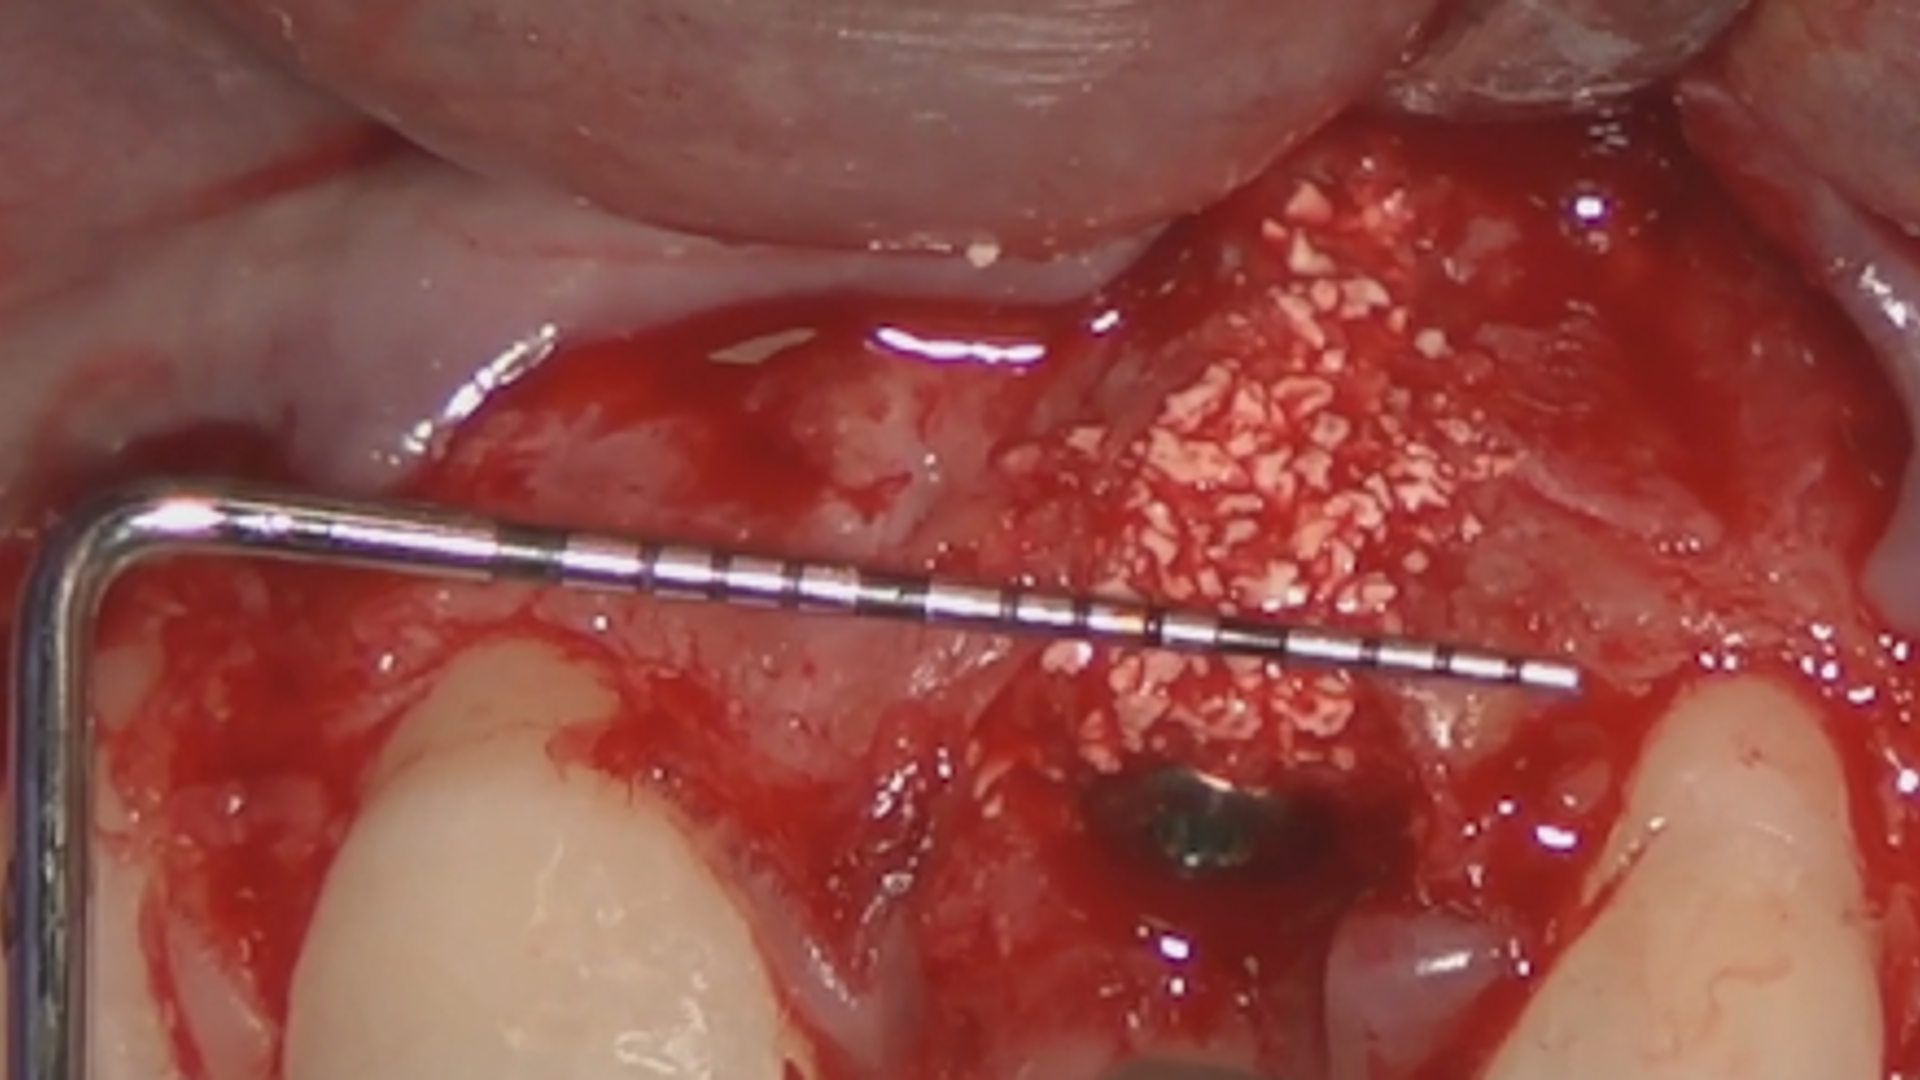

How to increase the supra-periosteal keratinized tissue

Hands-On Video Part 2 - Site-specific preparation for a guided implant placement

Hands-On Video Part 3 - Connective tissue graft harvesting and disepithelisation